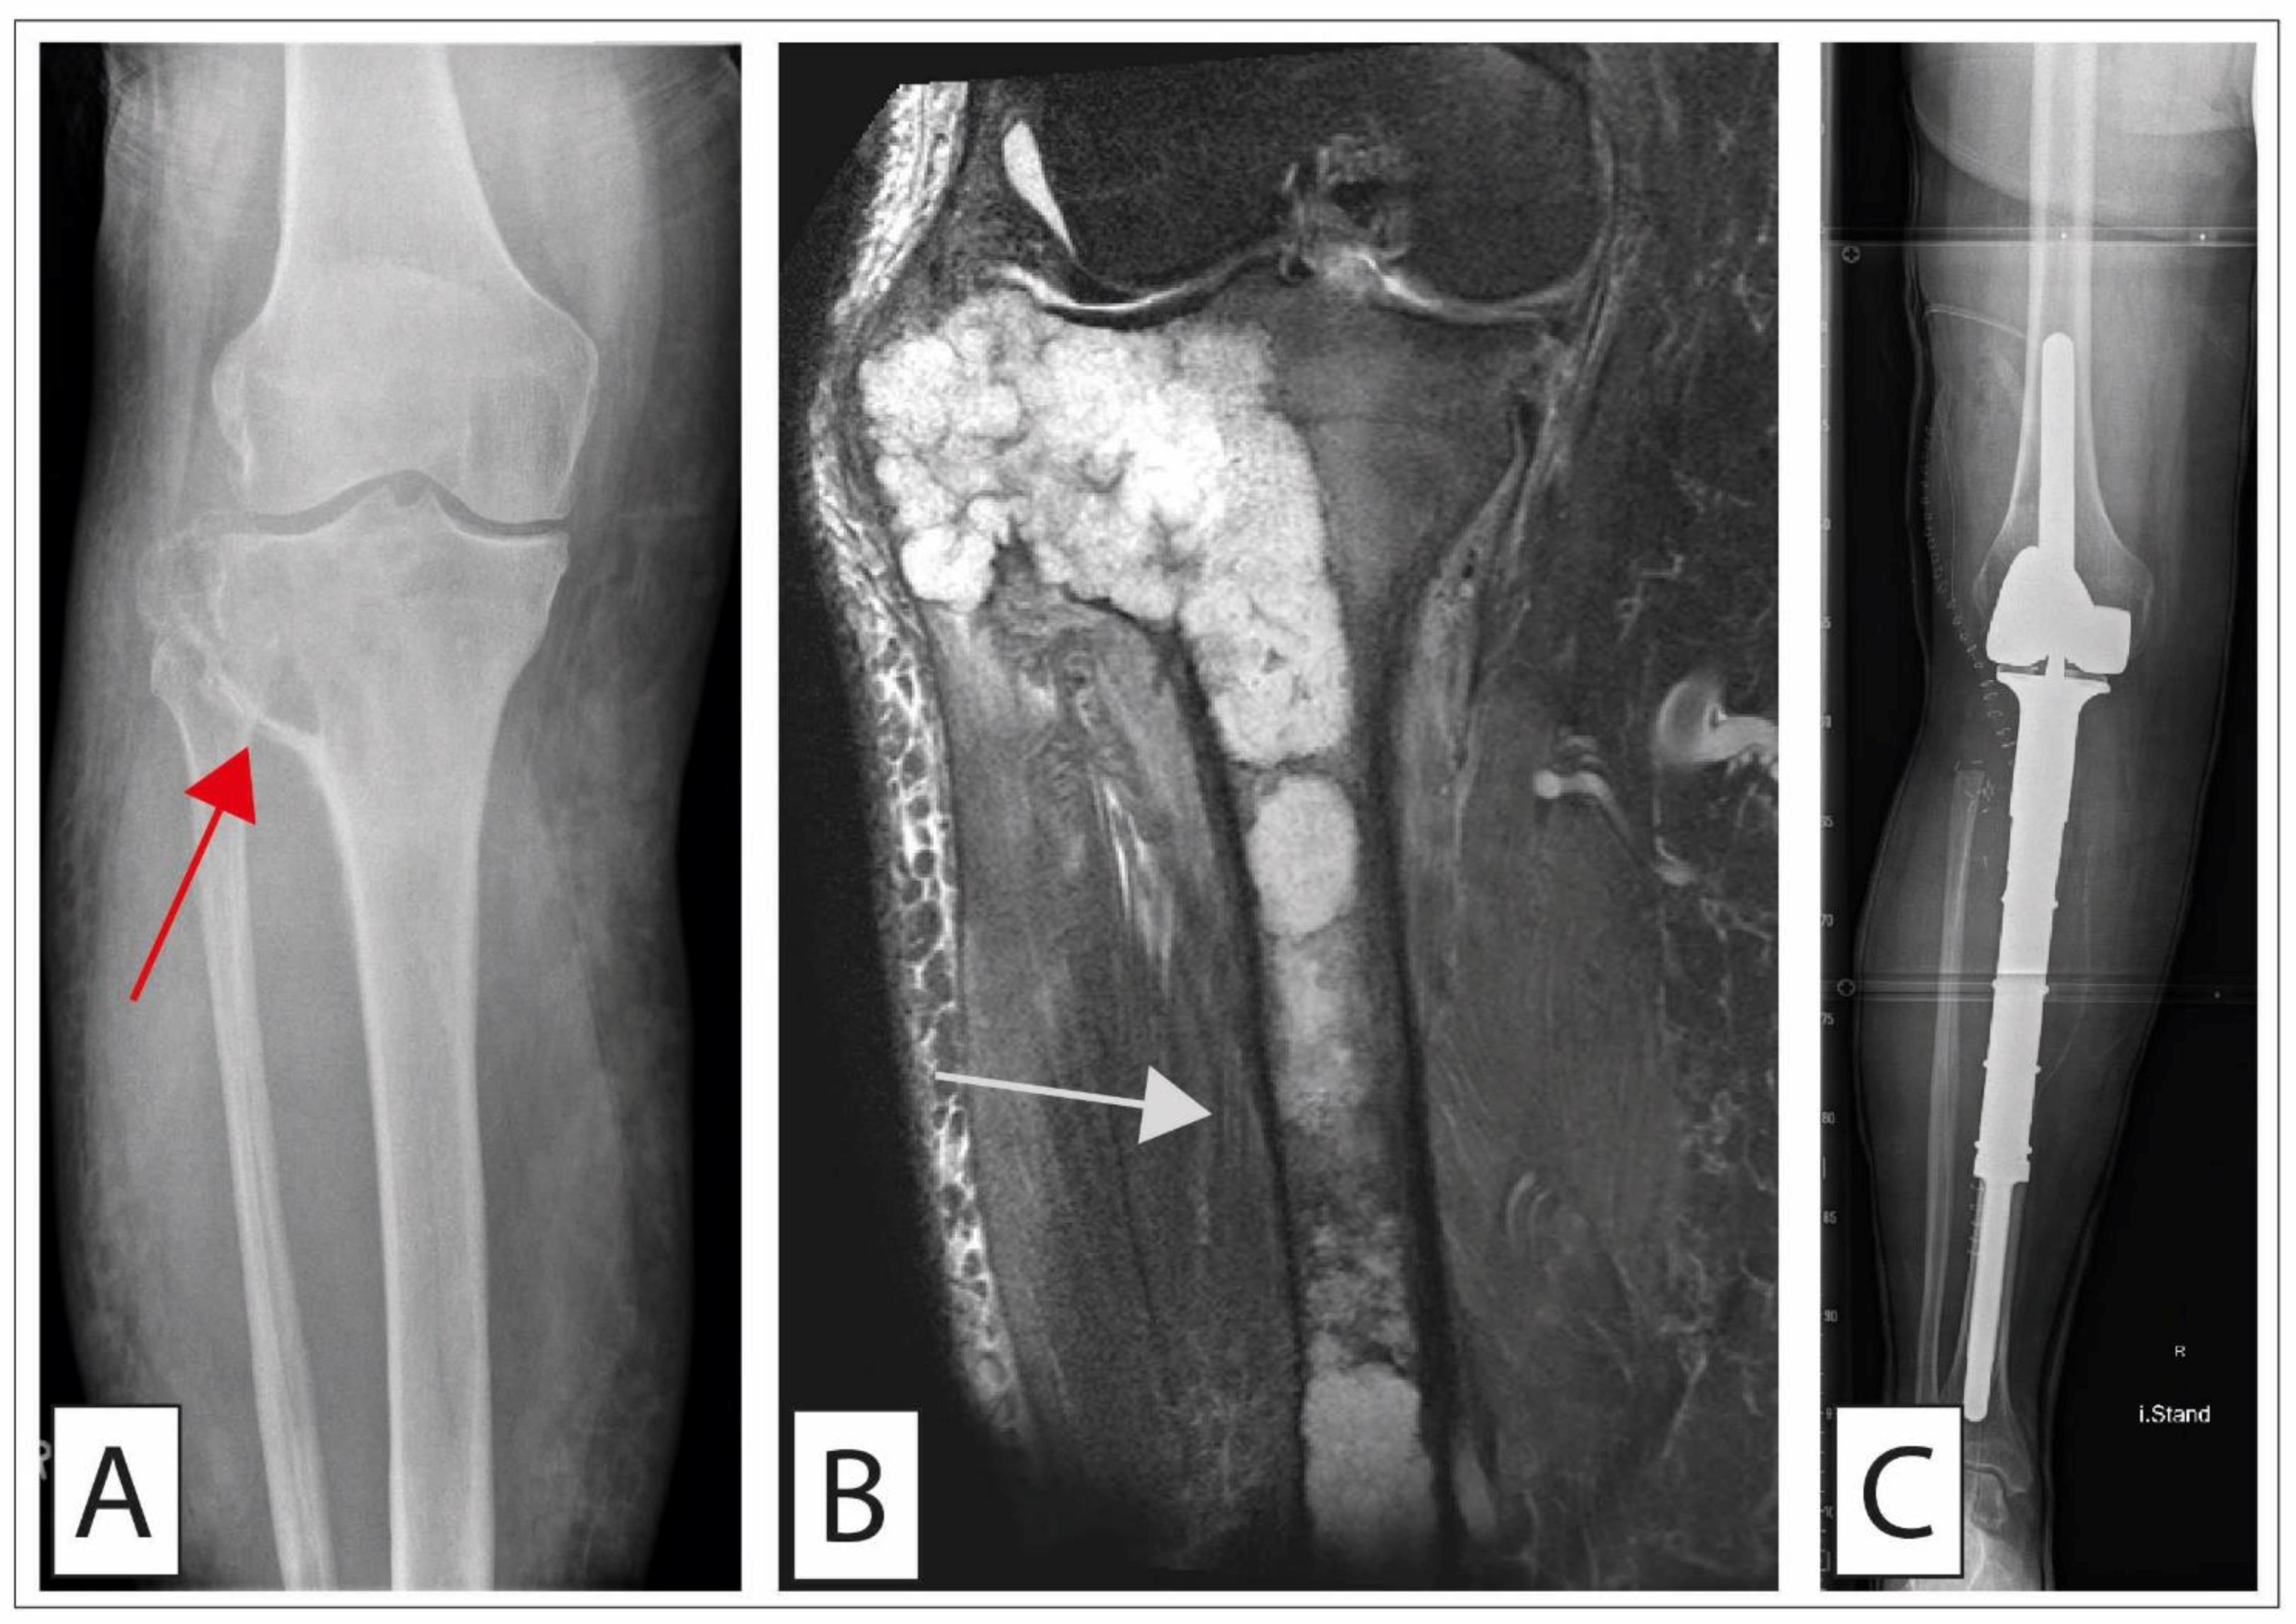

4.2.2. Surgical Treatment

Grade 1 malignancies should be treated by an extensive intralesional curettage with local adjuvant chemical treatment or cryotherapy/cementation. Higher local relapse rates have been described for curettage compared to resection with free margins, which is why some authors advocate marginal resection in the trunk-near region. Dierselhuis et al., in a 2019 Cochrane review, failed to show advantages of wide resection over curettage for lesions of the long bones [97]. Grade 2–3 chondrosarcomas as well as local relapses with an M0 situation are treated by wide resection [87,98] (Figure 4). Overall, the location of the tumor (e.g., pelvis or joints) determines the complexity of the surgical treatment and may subsequently require sophisticated surgical reconstruction techniques. Interestingly, in a recent study, Song et al. demonstrated a survival benefit for complete resection of the primary tumor for conventional G2 chondrosarcoma including 200 patients with an M1 situation from the SEER database [99]. In such a case, the resection of the primary tumor can be discussed with the patient. Navigation-assisted surgery represents a new emerging surgical tool that may help to achieve clear margins especially in complex tumor situations such as in the pelvic region. Preliminary studies using this technique have already reported a trend towards improved local tumor control and longer tumor-free survival [100]. Another study, by Sambri et al., observed, in a small cohort of 61 patients with G2 or 3 chondrosarcomas, that pulmonary metastasectomy may be associated with prolonged survival, suggesting that pulmonary metastasis surgery in cases with isolated metastases may also be critically discussed with the patient [101].

4.2.3. Surgical Treatment of Chondrosarcoma of the Pelvis

A unique situation is the presence of a central chondrosarcoma of the pelvic region (Figure 5). Chondrosarcomas of the pelvic region have an increased risk of metastasis and local recurrence (50% each). In addition, high demands are imposed on the surgeon for the surgical treatment since surgical procedures and reconstruction of the pelvic ring are highly complex [102]. A wide excision (>4 mm) should be the goal of surgical therapy, as smaller margins have an increased risk of early local relapse and of a reduced long-term survival [103]. At the same time, achieving these margins may entail the resection of nerves or nerve roots, which can be especially demanding for the patient in the case of the pudendal nerve. Subsequent reconstruction of the pelvic ring is challenging. Currently, reconstructions are performed by biological (e.g., hip transposition, massive allografts, autografts) or endoprosthetic reconstructions (e.g., allograft/prosthesis composites or prosthetic reconstructions). However, both allografts and autografts have a relevant risk of infection and/or fracture and often a postoperative leg length discrepancy is frequently observed [104]. Specially developed modular tumor prostheses demonstrated a reasonable functional outcome with long durability, with, however, also high infection rates [105]. Nevertheless, technical advances in design, structure, and fabrication have made such treatment strategies available for those patients affected by osteosarcoma of the pelvis.